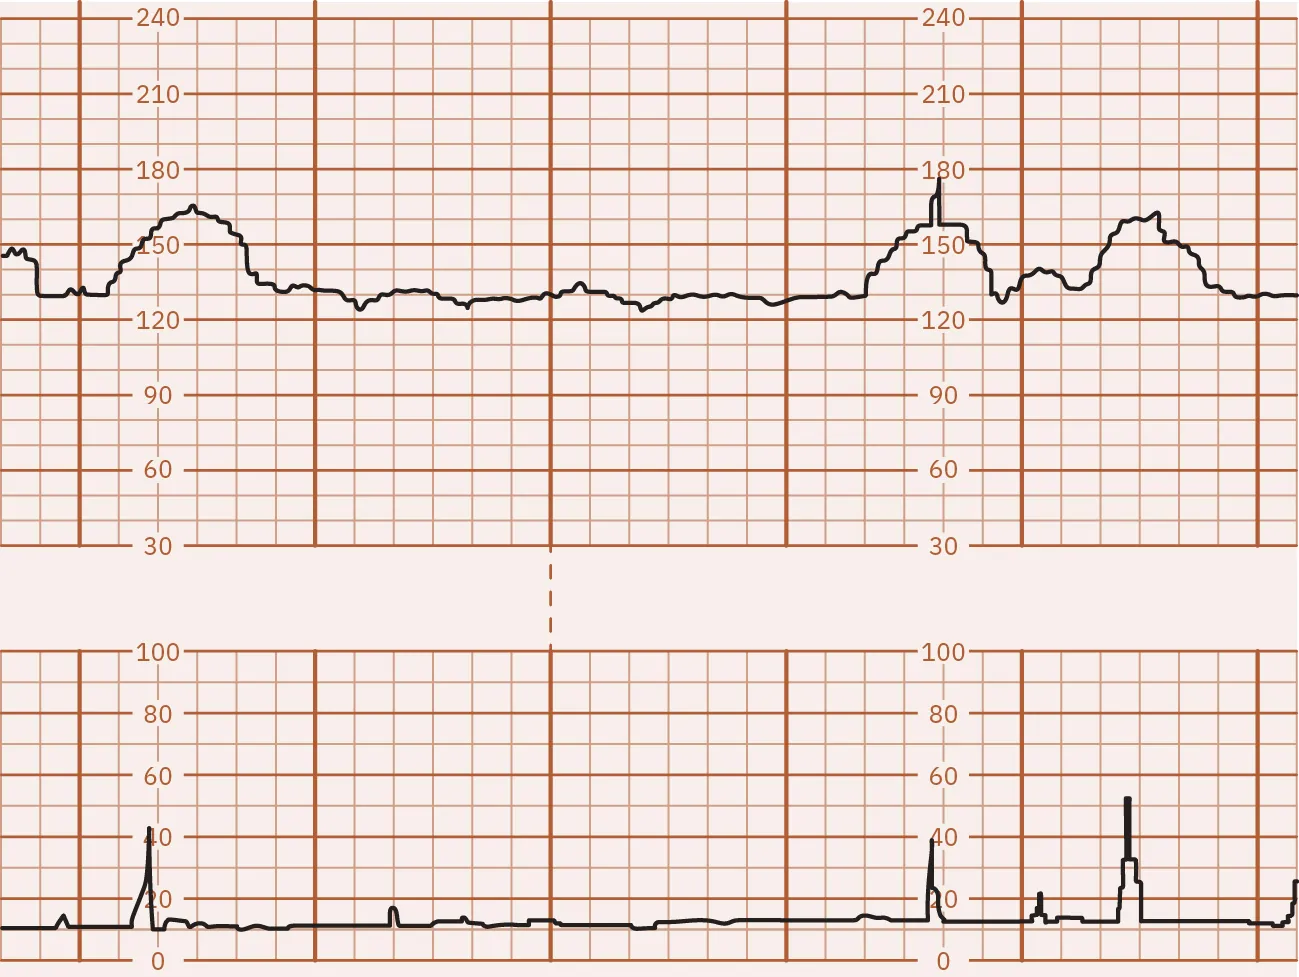

A nonstress test (NST) is a noninvasive test for fetal well-being that provides a graphic of the fetal heart pattern in relation to the movement of the fetus (Figure 13.10). The external fetal and uterine contraction monitor is used to perform an NST. This test places no stress on the fetus. A nonstress test can be performed starting at 28 weeksโ€™ gestation (U.S. National Library of Medicine, 2021a).

Fetal monitor tracing graphic depicting a reactive NST. Top strip indicates spikes at same times lower strip indicates spikes.

Figure 13.10 Reactive NST The FHR accelerations are linked with the fetal movements in the uterine contraction tracing. In this illustration, the FHR increased at least 15 beats per minute (bpm) above the baseline of 130 two or more times in this 10-minute tracing. (attribution: Copyright Rice University, OpenStax, under CC BY 4.0 license)

If the fetal heart rate increases by at least 15 bpm above the baseline for 15 seconds for a fetus at 32 weeks or greater, or 10 bpm for 10 seconds in the fetus less than 32 weeks, two or more times during a 20-minute testing period, it is considered a reactive NST and is a reassuring result. If there are insufficient accelerations of the fetal heart rate within the 20- to 40-minute window or the accelerations do not meet the required criteria, the NST is nonreactive. However, a nonreactive result does not necessarily indicate a health problem. The fetus may have been sleeping and not easily awakened. Certain medications taken during pregnancy may also cause a nonreactive result. The health-care provider will review the results and determine if additional testing is needed to find out if there is a cause for concern (U.S. National Library of Medicine, 2021a).

The nurse can help prepare the pregnant person for this test by explaining why the test is recommended and what happens during the test. The test may be done in the providerโ€™s office or at the hospital. The pregnant person will lie on a reclining chair or an exam table when the test is performed in the office or clinic. The nurse will attach two devices around the pregnant personโ€™s abdomen. One will measure the fetal heart rate, and the other will record the pregnant personโ€™s uterine activity. (See Chapter 16 Electronic Fetal and Uterine Contraction Monitoring for more information on external fetal monitoring.) The pregnant person will be instructed to press a button on a cable attached to the fetal monitor each time they feel the fetus move. If the test is reactive, the nurse will inform the health-care provider and provide the pregnant person with further education and instructions as prescribed.